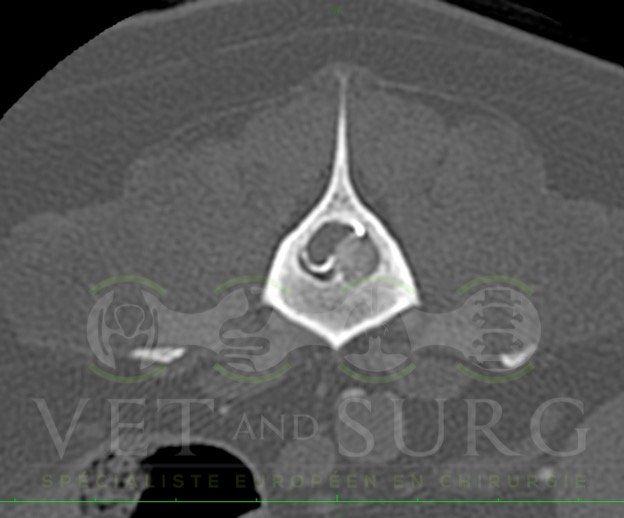

Hernie discale chez un bouledogue de 5 ans

Georges est présenté pour une paralysie des deux membres postérieurs.

Le scanner du rachis révèle une hernie discale en L3-L4 comprimant sévèrement la moelle épinière.